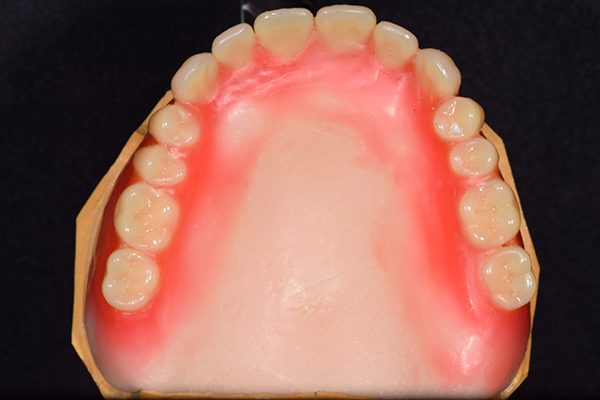

上の入れ歯(裏)

入れ歯は極力薄くするために金属を使用しました。しっかり噛める様にするため、ノンメタルクラスプデンチャーにはしませんでした。

金属を使用して、薄く違和感が少ない入れ歯が完成しました。 また、見た目にも気を使い、バネが見えにくい様な構造にしました。

義歯は下顎で、しっかり噛めること、違和感の少ないものという希望があったため、なるべく入れ歯を薄く作成するために金属をしようした義歯とした。

また、見た目もあまり義歯が目立たない様に、バネの部分を見えにくいように作成した。